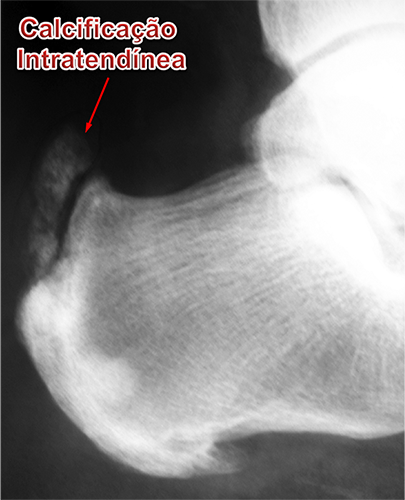

Calcificação Intratendínea (Esporão do Tendão de Aquiles) :

A calcificação intratendinea, popularmente chamada de esporão do tendão de Aquiles, forma-se por uma alteração celular degenerativa das fibras do tendão. Isto ocorre pela alternância, durante um longo período de tempo, entre os processos de inflamação, microrruptura e reparo local. Portanto, a constante tentativa de cicatrização de uma lesão crônica do tendão leva à sua degeneração e calcificação local de suas fibras.

As radiografias do tornozelo servem para avaliar as calcificações ao longo do trajeto do tendão, assim como erosões ósseas e a deformidade de Haglund do calcâneo quando presentes.